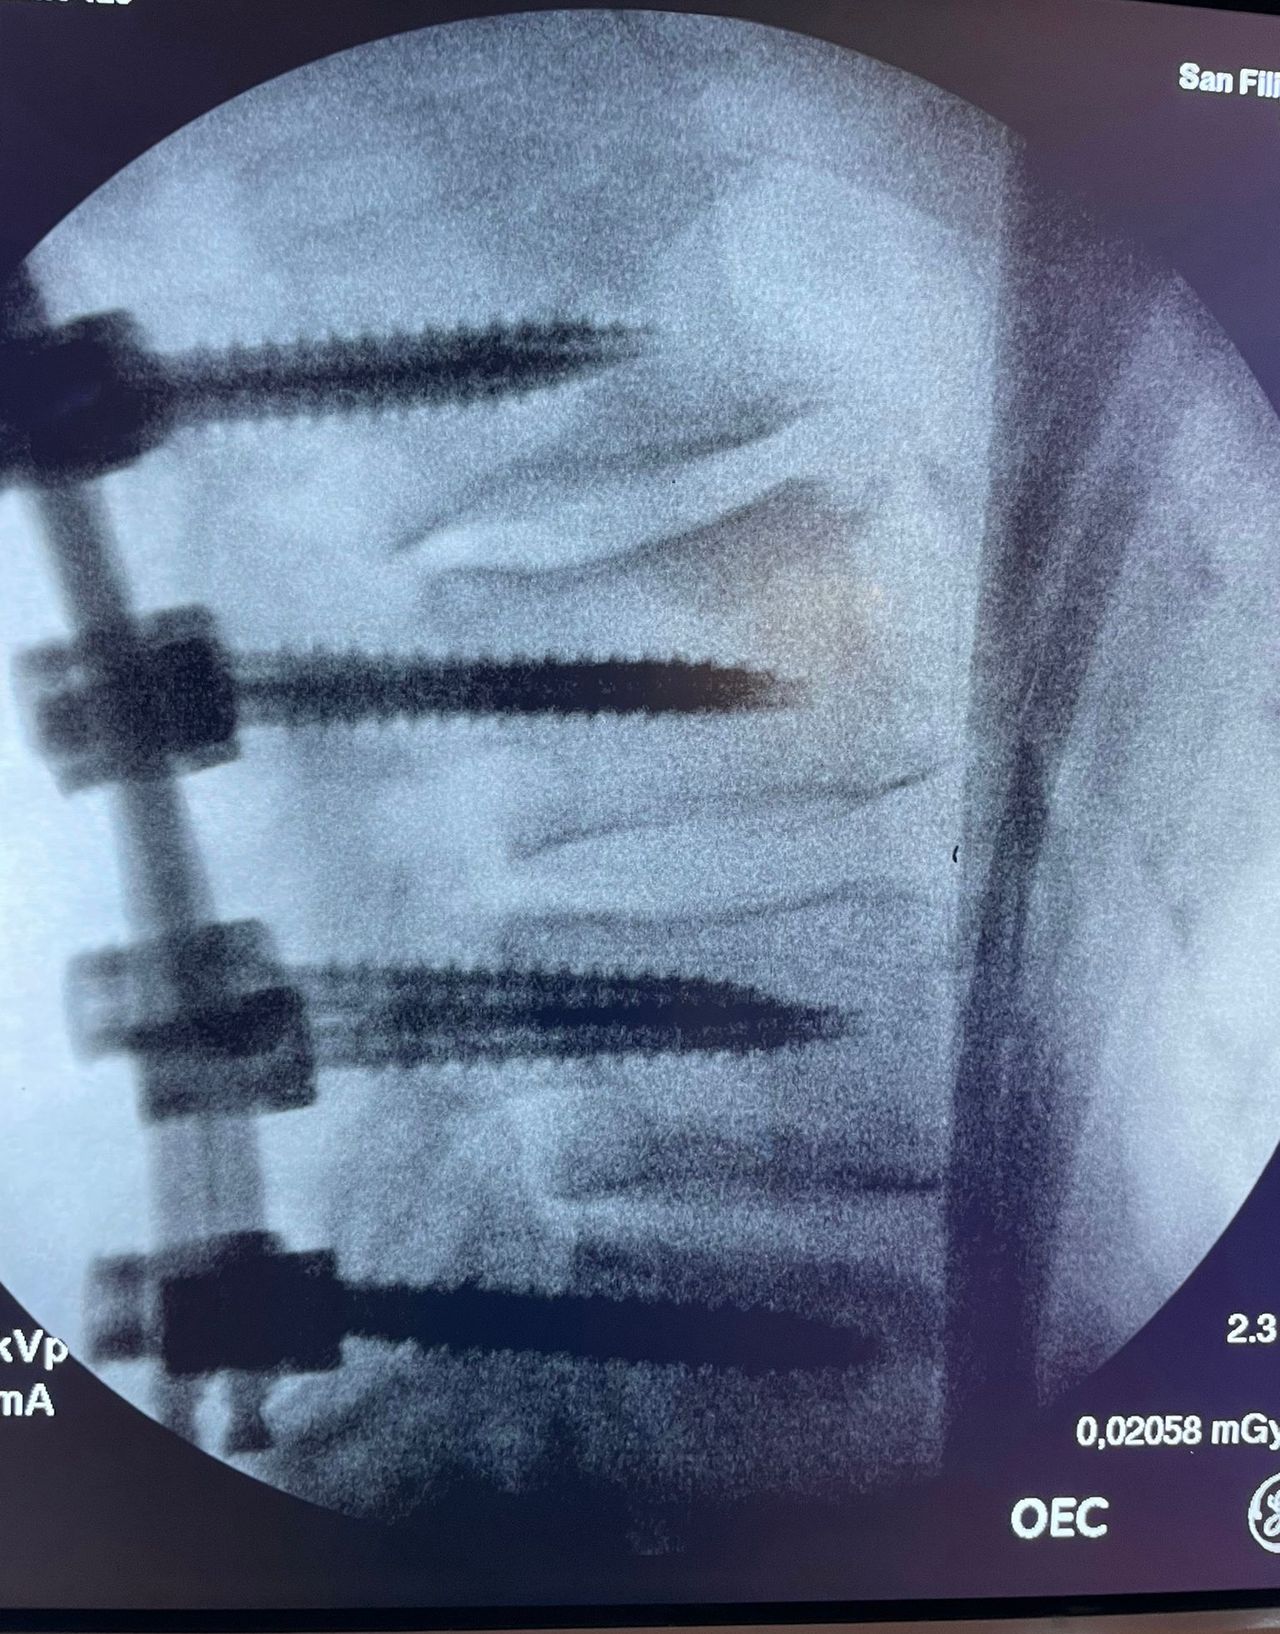

- Chirurgia Mininvasiva percutanea vertebrale - stabilizzazioni e artrodesi intersomatiche (per fratture vertebrali, spondilolistesi, instabilità vertebrali, discopatie)

- RX scopia intraoperatoria